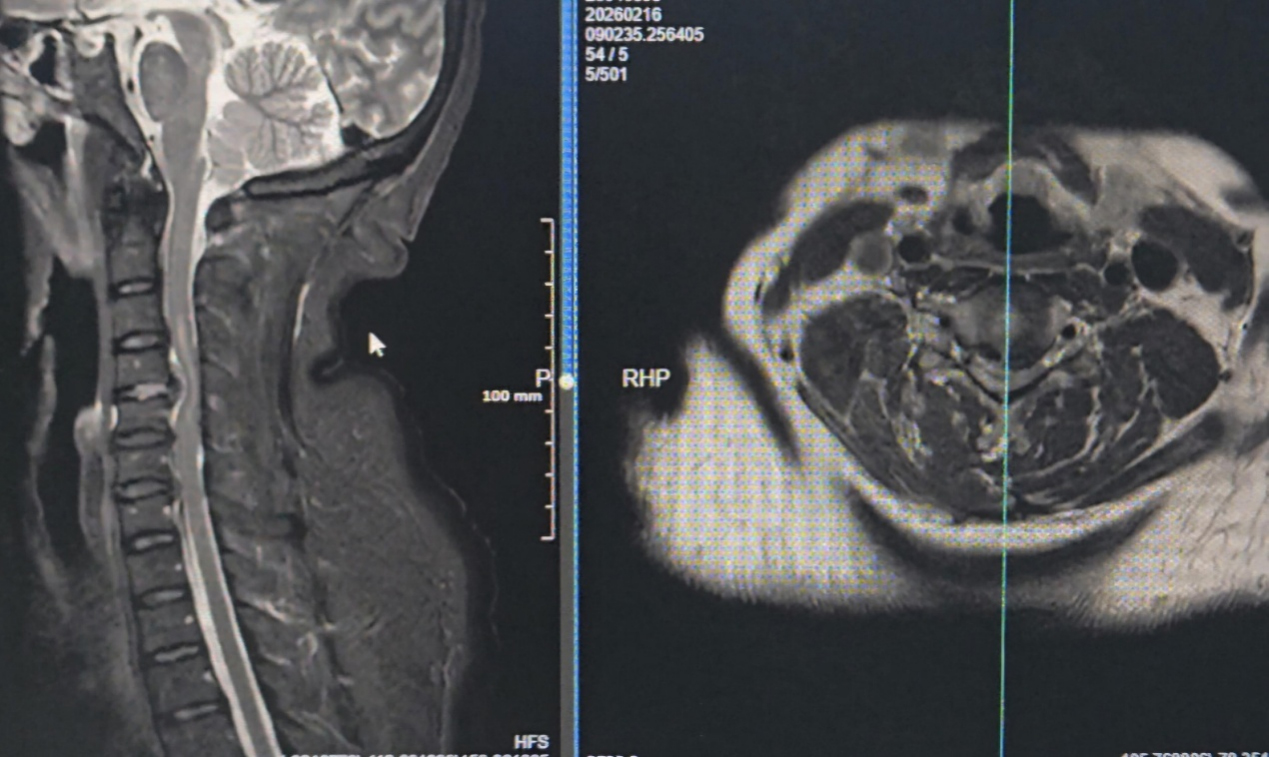

除夕当天,一名57岁女性患者因颈部疼痛加重伴四肢不全瘫踏上辗转求医路。患者三日前症状突发,当地医院检查考虑颈椎间盘急性脱出伴脊髓损伤,受限于救治能力建议转院,转诊途中患者还出现呼吸困难症状,病情危在旦夕。

家属带着患者紧急来到重庆市急救医疗中心骨科就诊,医生快速确诊后,判定其有急诊手术解除颈脊髓压迫的明确指征,医院当即开放绿色救治通道,各科室无缝衔接、高效配合,把“迅速、尽心”的院训落到实处,从患者入院到手术结束,仅用8个小时便成功解除颈脊髓压迫,阻止病情进一步恶化,为患者神经功能恢复赢得宝贵时机。